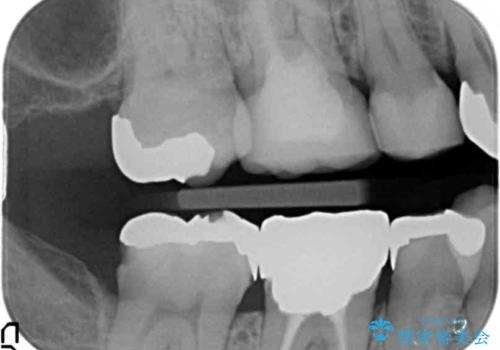

- 右下奥の銀歯の下が虫歯になっていました。

歯ぐきの下までしっかり修復するために、歯周外科手術を含めた治療を行いました。

歯ぐきの中まで虫歯の場合は、まず、虫歯も取りきることが難しいです。

また、被せ物のきわを歯ぐき深くに設定してしまうことになり、正確な歯型がそのままでは取れません。また、歯ぐきのみを取り除いても一時的な処置となり、また歯ぐきが再生してしまうため、最終的には歯ぐきの腫れが治りません。